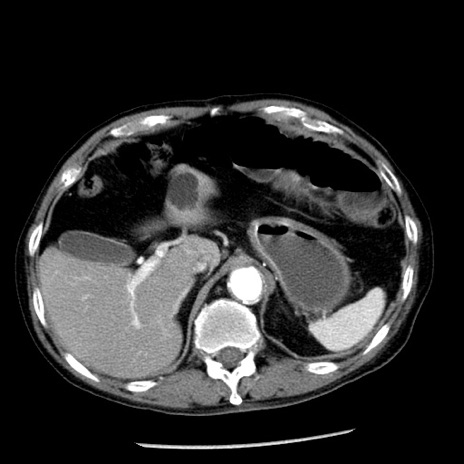

症例26(横断像)

【症例】80歳代男性

【主訴】嘔吐

【現病歴】昨晩2回嘔吐あり、今朝になっても嘔吐あり。来院。

【既往歴】胃潰瘍

【身体所見】意識清明、BT 37.6℃、BP 166/95mmHg、HR 100bpm、SpO2 97%、腹部:平坦・軟、腸蠕動音聴取良好、圧痛なし。

【データ】WBC 21900、CRP 1.46